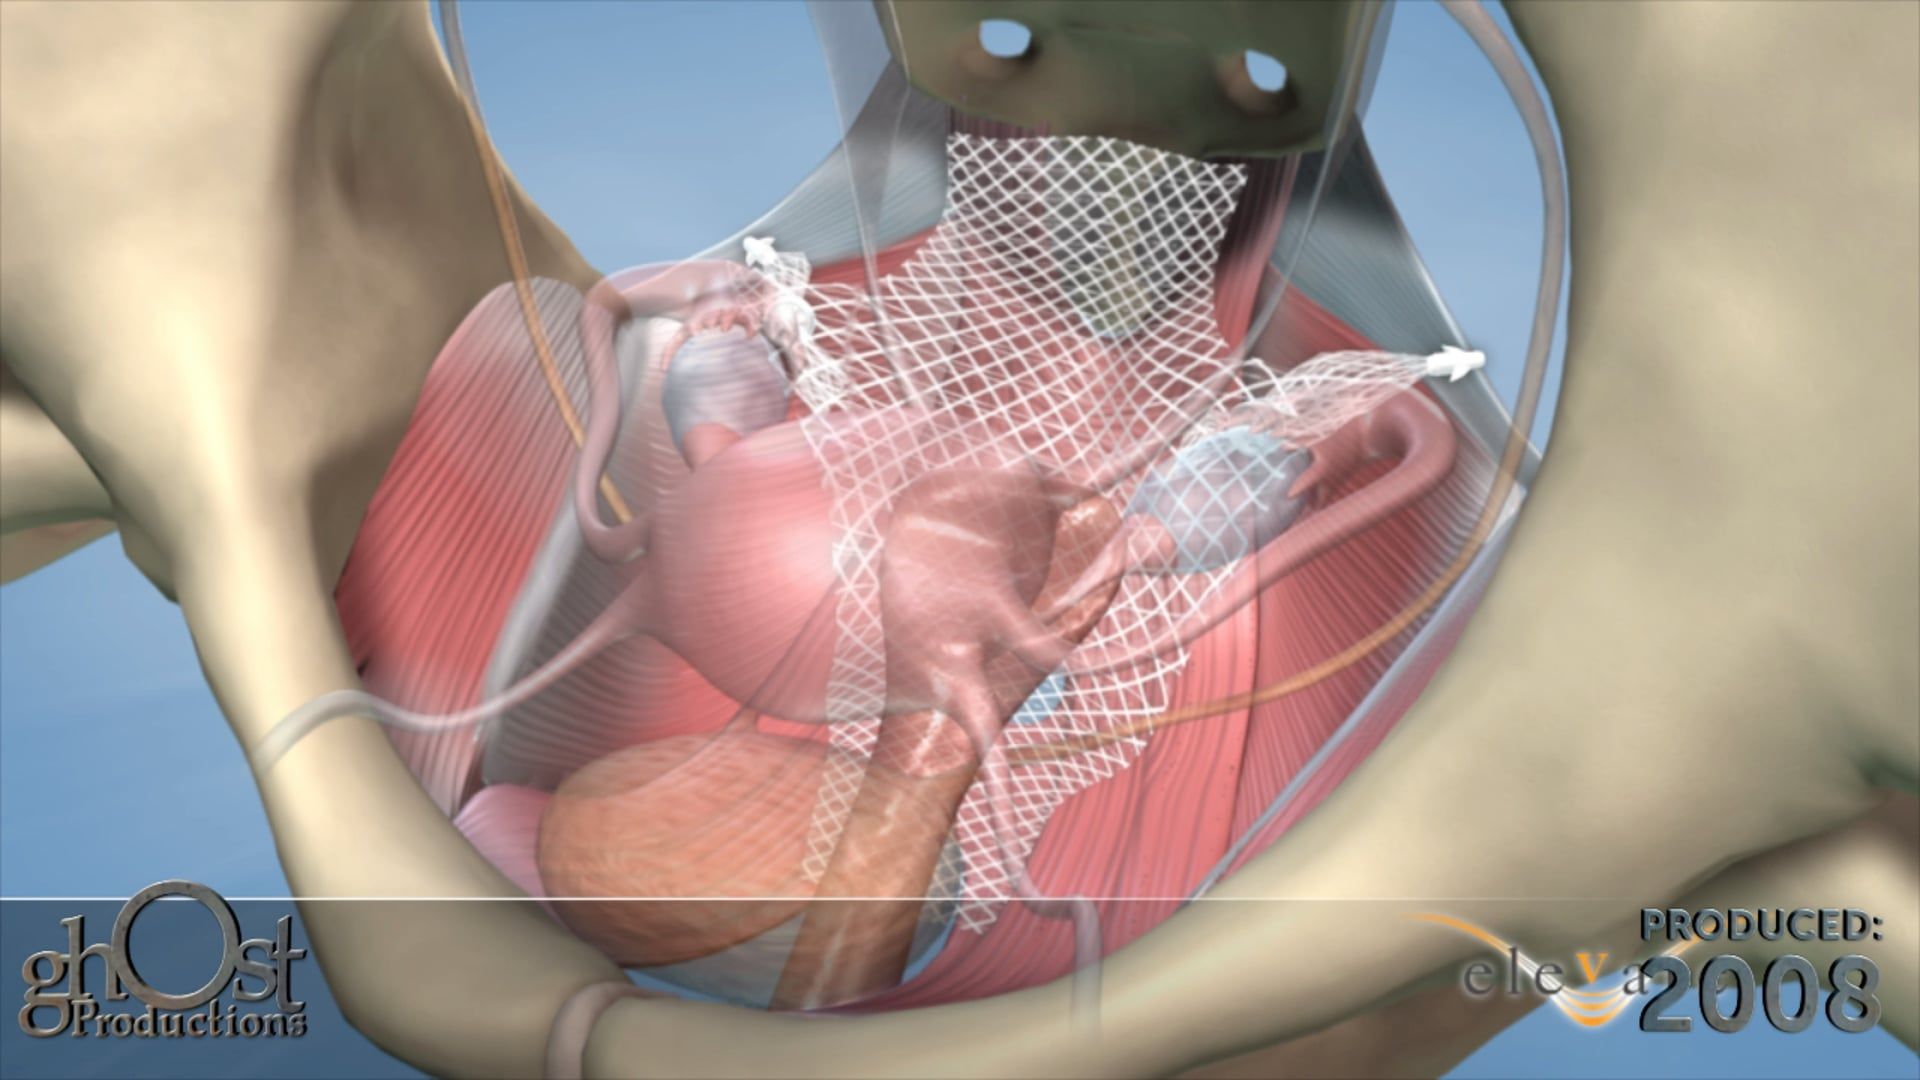

AMS partnered with Ghost Productions, a medical animation and graphics company, to create a series of animations and medical graphics that effectively communicated the benefits of their products. Ghost Productions worked closely with AMS's team to understand the mechanism of action of each product and create a visual representation of the process.

the animations and medical graphics produced by Ghost Productions proved to be instrumental in helping AMS effectively communicate the benefits of their products to their target audience. The visual aids helped potential customers and physicians understand the mechanism of action of each product and the benefits of using them to treat urological and gynecological conditions.